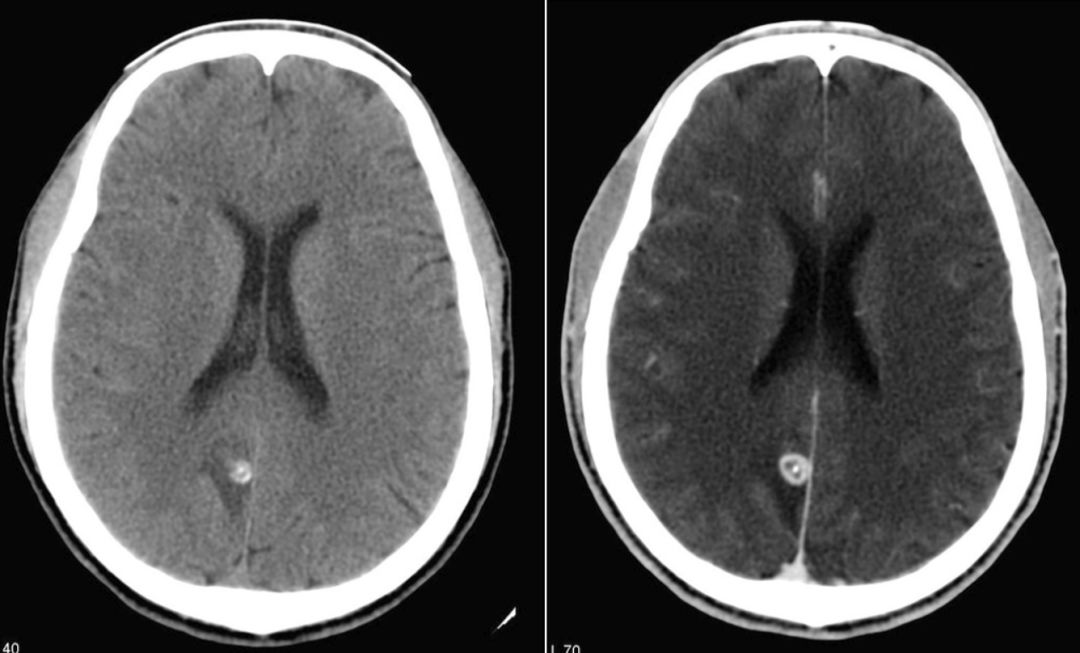

囊虫的钙化形态各异,取决于脑囊虫四个主要阶段(也称为Escobar的病理阶段):a囊泡期:活的寄生虫有完整的包囊膜,囊壁光滑,内可见头节,无强化。因此没有宿主反应。b胶状囊泡期:包囊破溃,包囊的液体渗入组织,周围有水肿。此期引发强烈的免疫反应,所以此期的临床反应最重。见下图。

c颗粒结节期:随着囊肿进一步变性缩小,水肿减轻;增强仍存在。d结节钙化期:终末期,静止的钙化囊残余;没有水肿。